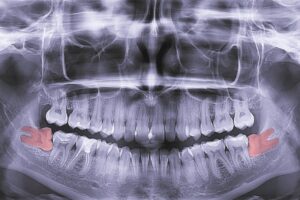

x-ray of teeth, molar tooth improperly growing, absence of the eighth molar